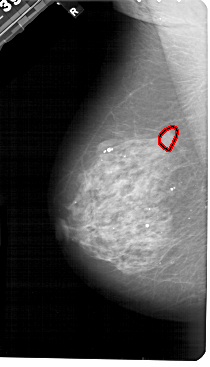

FILE: A_1488_1.LEFT_MLO.OVERLAY

TOTAL_ABNORMALITIES 1

ABNORMALITY 1

LESION_TYPE MASS SHAPE IRREGULAR MARGINS ILL_DEFINED

ASSESSMENT 4

SUBTLETY 2

PATHOLOGY MALIGNANT

TOTAL_OUTLINES 1

BOUNDARY